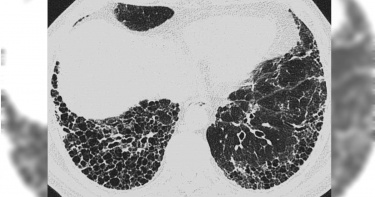

俗稱「菜瓜布肺」的肺纖維化若未即時就醫治療,5年存活時間竟比許多癌症還低!台灣胸腔暨重症加護醫學會理事長王鶴健也示警,肺纖維化的初期咳嗽症狀,很容易被當成小感冒而延誤就醫,因此呼籲民眾若有出現「咳、喘、累」3大症狀,且狀況持續8週以上,就應儘快到胸腔內科檢查。據《NOW健康》的報導,肺纖維化的發展過程會由肺底往肺尖方向移動、周邊往中心方向蔓延,「就像溫水煮青蛙一般」。王鶴健也分享親身案例指出,有名病患是企業高階主管,平時有咳、喘症狀,自認身體硬朗還能負荷,便不以為意。再加上當時沒有「聽診後背下肺葉」的完整檢查觀念,直到有次健檢才發現CA19-9指數偏高,誤以為是惡性腫瘤,轉診至胸腔內科才發現確診「特發性肺纖維化」,很快病情急速惡化,不到1年就病逝。王鶴健強調,「特發性肺纖維化」是不可逆的!病友容易因外部因素刺激導致肺功能急速下降,嚴重者走幾步路就覺得氣喘吁吁,甚至感到呼吸困難,由於疾病進展因人而異且變化多端,若未及早發現並適當治療,5年存活時間比許多癌症還低。王鶴健進一步解釋,目前「特發性肺纖維化」的成因尚不清楚,但50歲以上男性、有吸菸史、肺纖維化家族病史、長期胃食道逆流或是曾暴露於高粉塵環境工作者,都是高危險族群。尤其當肺部開始有纖維化的跡象,醫師在聽診後背下肺葉時,就會聽到有如魔鬼氈撕開的聲音。中華民國風濕病醫學會理事長鄭添財也強調,自體免疫疾病病友也是肺纖維化的高風險族群。自體免疫疾病病友因免疫系統錯亂,導致疾病敵我不分地攻擊器官,一旦侵犯到肺部就可能發生肺纖維化,若未及時治療將進展為「漸進性肺纖維化」。提醒病友對於呼吸道症狀或身體異狀千萬不可掉以輕心。鄭添財也強調,病友也要配合醫囑,若有症狀都要即時向醫師反應,切勿自我診斷,錯失黃金治療時機。對此專家也提供「護肺3招」,包括民眾若有「咳、喘、累」3大症狀務必提高警覺;高危險族群也應落實「聽診後背下肺葉」的完整檢查;自體免疫患者更是每3至6個月就要定期安排肺功能檢查。此外,慢性阻塞性肺病(COPD)也易遭大眾忽略,建議民眾若出現「濕咳、多痰、易喘」症狀且持續達3週以上,就請儘快就醫求診。

你常忽略咳嗽、喘不過氣等肺部症狀嗎?近年國人對於「肺纖維化」這個名詞已不陌生,但初期症狀不明顯,容易與其他呼吸道疾病混淆,甚至誤當成小感冒而不以為意,導致延誤治療。台灣胸腔暨重症加護醫學會今年首度攜手社團法人中華民國風濕病醫學會,於919台灣肺纖維化日前夕9/17(日)在大安森林公園舉辦「肺常有意思 健走嘉年華」活動。呼籲國人應建立正確肺部健康觀念,留意「咳、喘、累」三大症狀外,也應定期檢測肺功能。比許多癌症更致命 醫授護肺三招俗稱「菜瓜布肺」的肺纖維化,成因非常多元,較為大眾所熟知的有發病原因不明的「特發性肺纖維化」。台灣胸腔暨重症加護醫學會理事長王鶴健醫師表示:「特發性肺纖維化不可逆,病友容易因外部因素刺激導致肺功能急速下降,嚴重者走幾步路就覺得氣喘吁吁,甚至感到呼吸困難,由於疾病進展因人而異且變化多端,若未及早發現並適當治療,五年存活時間比許多癌症還低。」社團法人中華民國風濕病醫學會理事長鄭添財醫師強調,自體免疫疾病病友也是肺纖維化的高風險族群,提醒病友對於呼吸道症狀或身體異狀千萬不可掉以輕心。為提高大眾對於肺部健康的警覺,健走日當天活動現場醫師更傳授護肺三招,教大家為自己的肺部健康把關!第一招:出現「咳喘累」可能是肺正發出求救訊號肺纖維化常見症狀為「咳、喘、累」,臨床觀察到,民眾往往都要咳到無法入睡,或是打擾到別人時才願意就醫諮詢,一旦確診為肺纖維化,此時肺功能早已嚴重下降,不僅要透過補充氧氣來維持日常活動外,嚴重者還需住院插管治療;此外,慢性阻塞性肺病(COPD)也是大家容易忽略的嚴重呼吸道疾病,民眾如出現「濕咳、多痰、易喘」症狀且持續達三周以上,也請儘快到胸腔內科尋求專業診療。▲「肺常有意思 健走嘉年華」齊走畫面第二招:高危險群應落實「聽診後背下肺葉」的完整檢查肺纖維化的發展過程是由肺底往肺尖方向移動、周邊往中心方向蔓延,「就像溫水煮青蛙一般!」王鶴健醫師分享曾收治一名企業高階主管,平時就有咳、喘症狀,自認身體還很硬朗仍能負荷這些小問題就不以為意,也沒有「聽診後背下肺葉」的完整檢查觀念,在一次健康檢查時發現CA19-9指數偏高,誤以為是惡性腫瘤,轉診至胸腔內科才發現肺部已嚴重纖維化,並確診特發性肺纖維化,很快地病情發生急性惡化,不到一年即病逝。目前特發性肺纖維化的成因尚不清楚,但50歲以上男性、有吸菸史、肺纖維化家族病史、長期胃食道逆流或是曾暴露於高粉塵環境工作者,都是罹患特發性肺纖維化的高危險族群。王鶴健醫師指出,當肺部開始有纖維化的跡象,醫師在聽診後背下肺葉時,就可聽到有如魔鬼氈撕開的聲音,若有出現「咳、喘、累」三大症狀且已經持續八週以上,儘快到胸腔內科檢查,當醫師懷疑是特發性肺纖維化者,則會進一步安排高解析度電腦斷層掃描以判斷是否確診與疾病侵犯的範圍。第三招:自體免疫疾病者 應定期肺功能檢查自體免疫疾病病友因免疫系統錯亂而導致敵我不分地攻擊全身器官,侵犯到肺部就可能發生肺纖維化。鄭添財醫師呼籲類風濕性關節炎、硬皮症、乾燥症、皮肌炎、多發性肌炎、紅斑性狼瘡等自體免疫疾病病友,無論是否出現「咳、喘、累」症狀,都建議在醫師的專業評估下,每3-6個月定期安排肺功能檢查,追蹤觀察是否有肺纖維化的狀況。鄭添財醫師也感嘆地提起過去曾有一名硬皮症病友,在類固醇等傳統藥物治療下,硬皮症狀得到控制,但肺部纖維化卻持續進展,肺功能如自由落體般的快速下降,隨著身體衰退、病情惡化,還來不及得到有效治療即抱憾離世。雖然肺纖維化無法根治,對肺功能的傷害亦不可逆,所幸近年已有抗肺纖維化藥物可協助病友改善症狀,恢復生活品質外,更能延緩肺功能下降程度,避免疾病持續惡化,鄭添財醫師強調,病友也要配合醫囑,若有症狀都要即時向醫師反應,切勿自我診斷,錯失黃金治療時機。